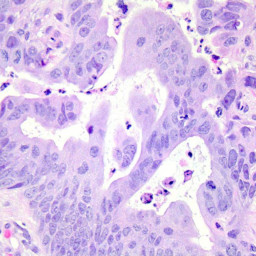

Benin 99,05%Adenocarcinome 99,63for 8328 images